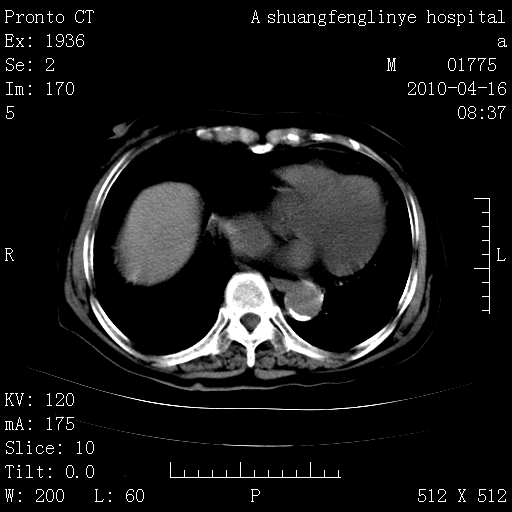

陈旧性结核,胃腔扩大,脾脏受压后移

慢支肺气肿,左上陈旧性结核,主动脉冠脉钙化

1)左肺上叶结核(纤维、增殖病灶)。2)冠状动脉及主动脉钙化。

1)左肺上叶结核(纤维、增殖病灶)。2)冠状动脉及主动脉钙化。肺动脉高压